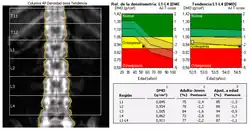

Osteopenia é uma condição fisiológica característica pela diminuição da densidade mineral, principalmente de cálcio e fósforo dos ossos, precursora da osteoporose. Classifica-se osteopenia quando a massa óssea é de 10% a 25% menor que a considerada normal. Mais do que isso, classifica-se como osteoporose.